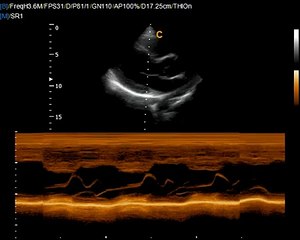

Chison Sontotouch 30 Touch screen color doppler Ultrasound